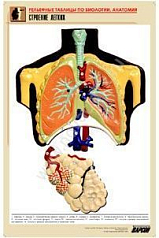

Комплект включает в себя 21 таблицу следующего содержания:

14. Строение легких;